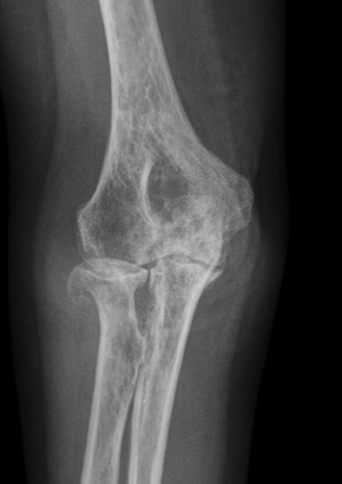

Bei degenerativen Veränderungen spricht man auch von Abnutzungserscheinungen, die bis zu einem gewissen Maß den natürlichen Prozess des Alterns darstellen. Degenerative Schädigungen sind übermäßige Abnutzungserscheinungen und können im Gelenkbereich (Arthrosen), an der Wirbelsäule (zum Beispiel Spondylarthrose, LWS-Syndrom) und an bestimmten Gewebsstrukturen wie Menisken, Kreuzbändern oder Nerven entstehen. Auslöser degenerativer Schädigungen sind beispielsweise Fehlstellungen, Überlastung, Muskelschwäche, fehlverheilte Brüche und Stoffwechselerkrankungen.